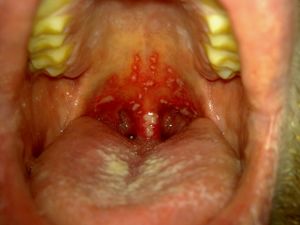

| Kwashiorkor sufferers show signs of thinning hair, edema, inadequate growth, and weight loss. The stomatitis on the pictured infant indicates an accompanying Vitamin B deficiency | |

التهاب الفم Stomatitis، هو التهاب يصيب الفم والشفتين.[1] ويشير إلى عملية التهاب تؤثر على الغشاء المخاطي للفم والشفتين، بدون حدوث تقرحات بالفم.[2]